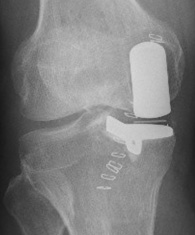

從膝關節疼痛到行走自如,一起來了解一下人工膝關節置換手術

很多人到了六七十歲,最先感到疼痛的就是膝蓋。大家可能都聽說過人工膝關節置換手術。但其實,關節置換手術又分為「全膝關節置換手術」和「單髁膝關節置換」,單髁膝關節置換比起全膝關節置換手術,有創傷更小、恢復更快的優勢。

單髁置換怎樣做?

單髁置換就像給膝蓋「補牙」——僅替換磨損的軟骨和少量骨質,保留健康組織和韌帶。